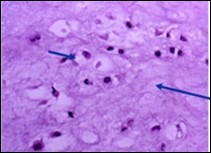

Figure 8.Enchondroma delineating hyaline cartilaginous cells with vacuolated cytoplasm and uniform nuclei 16.